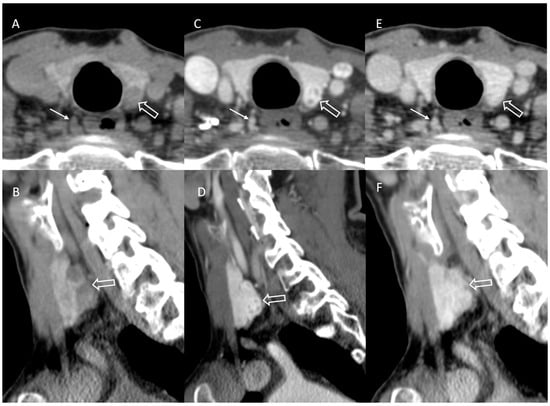

3.4. Incorrect or Incomplete Localization